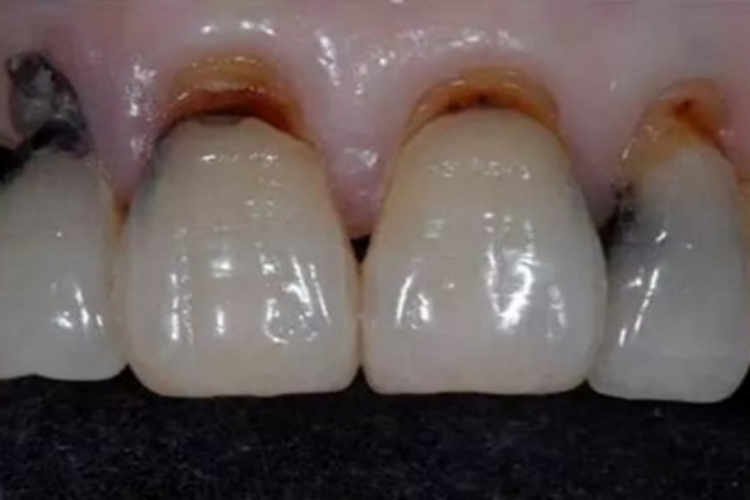

楔状缺损可引起牙龈萎缩,并且牙龈与牙的交界处因缺损产生肿胀、发黑的表现,随年龄增长,楔状缺损有增加的趋势。

楔状缺损可使得牙齿颈部敏感的牙本质暴露在外界环境中,容易受到热、冷、酸性和机械性刺激,进而引发炎症反应。牙齿颈部的牙本质受到炎症刺激后,会出现血管扩张,血流量增加,导致牙龈组织充血与水肿。而充血的血管在光线下会显露出黑褐色,从而使牙龈呈现萎缩发黑的现象。